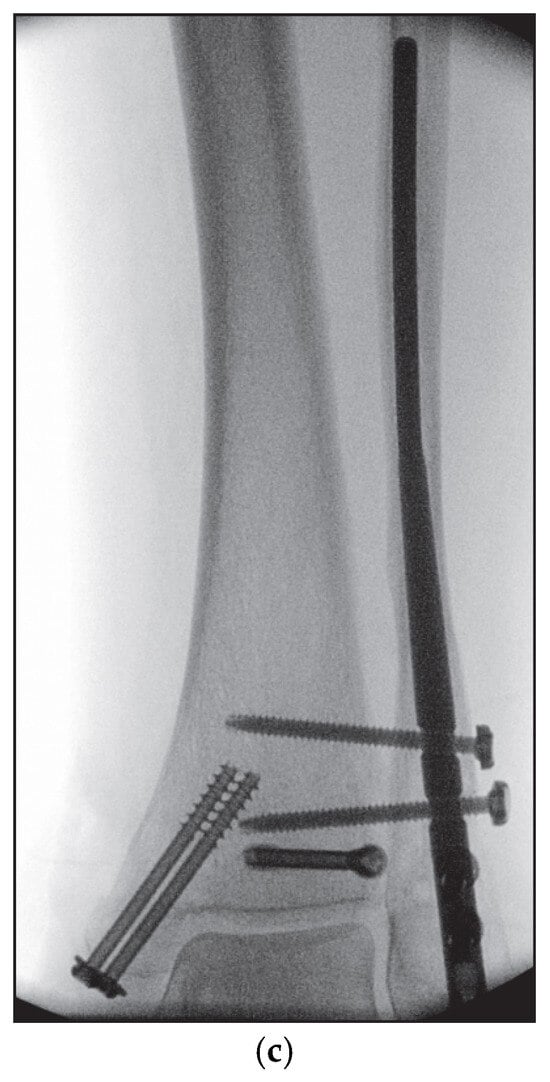

5.1. Surgical Considerations

5.2. Inside-Out Fixation of the Posterior Malleolus Using a Headless Double-Threaded Compression Screw

5.4. Medial Malleolar Cancellous Screw Fixation Using the Modified Posteromedial Approach

5.5. Reamed Intramedullary Locking Nail Fixation of the Distal Fibular Fracture